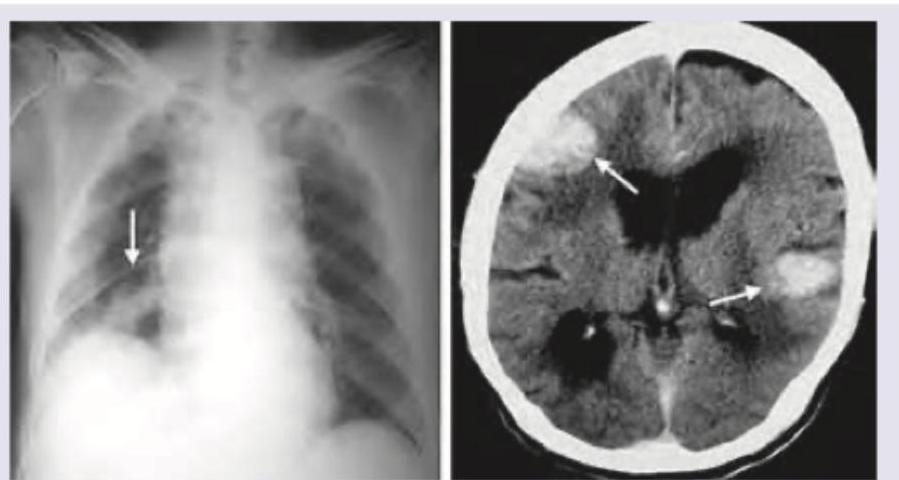

A 65-year-old uranium miner presents with muscle cramps and early morning headache. CXR and NCCT scan done shows:

Explanation: ***SCLC, brain metastasis*** - The chest X-ray shows a **hilar mass** (arrow), which is characteristic of **small cell lung cancer (SCLC)**, common in **uranium miners** due to **radon exposure**. - The NCCT scan reveals multiple **intracranial masses** (arrows) with surrounding **edema**, highly suggestive of **brain metastasis**, a frequent complication of SCLC, and explaining the **early morning headache** and potentially the **muscle cramps** (due to SIADH, a paraneoplastic syndrome common with SCLC). *NSCLC, brain metastasis* - While **Non-small cell lung cancer (NSCLC)** can also metastasize to the brain, the typical presentation is often different, and SCLC is more aggressively metastatic, especially to the brain, and strongly associated with the patient's occupational history as a **uranium miner**. - NSCLC often presents with **peripheral lung masses**, whereas the image shows a central hilar mass more indicative of SCLC. *Pleural and intracranial calcification* - The imaging does not clearly show **pleural calcification**; instead, a distinct hilar mass is present on the CXR. - The intracranial lesions are enhancing masses with edema, not calcifications, which would appear as much brighter, dense areas on CT. *Glioblastoma multiforme, extracranial spread* - **Glioblastoma multiforme** is a primary brain tumor and rarely spreads outside the central nervous system, making **extracranial spread** highly improbable. - The presence of a **primary lung lesion** makes brain metastasis from a systemic cancer much more likely than a primary brain tumor with rare extracranial involvement.